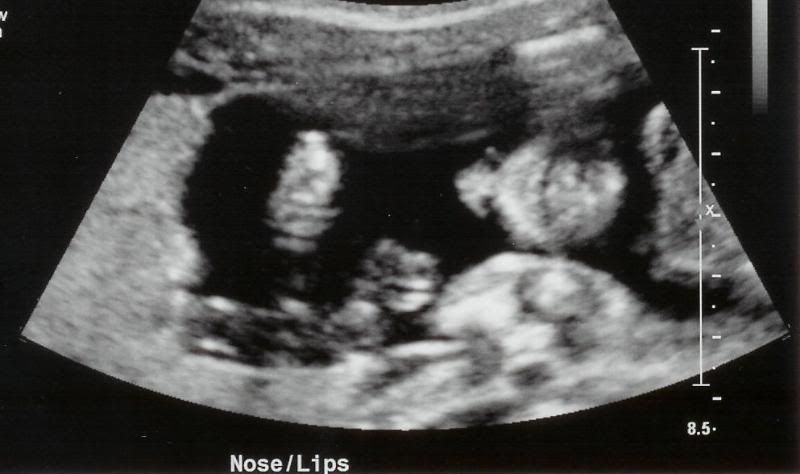

The Ultrasound this morning went wonderfully. The gender of the baby was written down on a card and sealed up without me looking! Also included is a picture of the baby. The U/S technician was so wonderful to me when I told him you were deployed that he printed out 5 pictures for me. You remember with Autumn, they would only give you one. The baby's heart rate measured anywhere from 139 to 144 beats per minute. I saw the head, spine, eye sockets, nose, lips, hands, kidneys, stomach, legs, feet, arms and the most astonishing was the heart. All four chambers beating beautifully. The technician seemed to spend a lot of time around the brain area and I don't know if that means anything or not because they spent a lot of time looking around Autumn's heart last time and this time, not so much. I will get to review the results of my U/S with my doctor in two weeks. Here are the pictures:

The nose and lips.